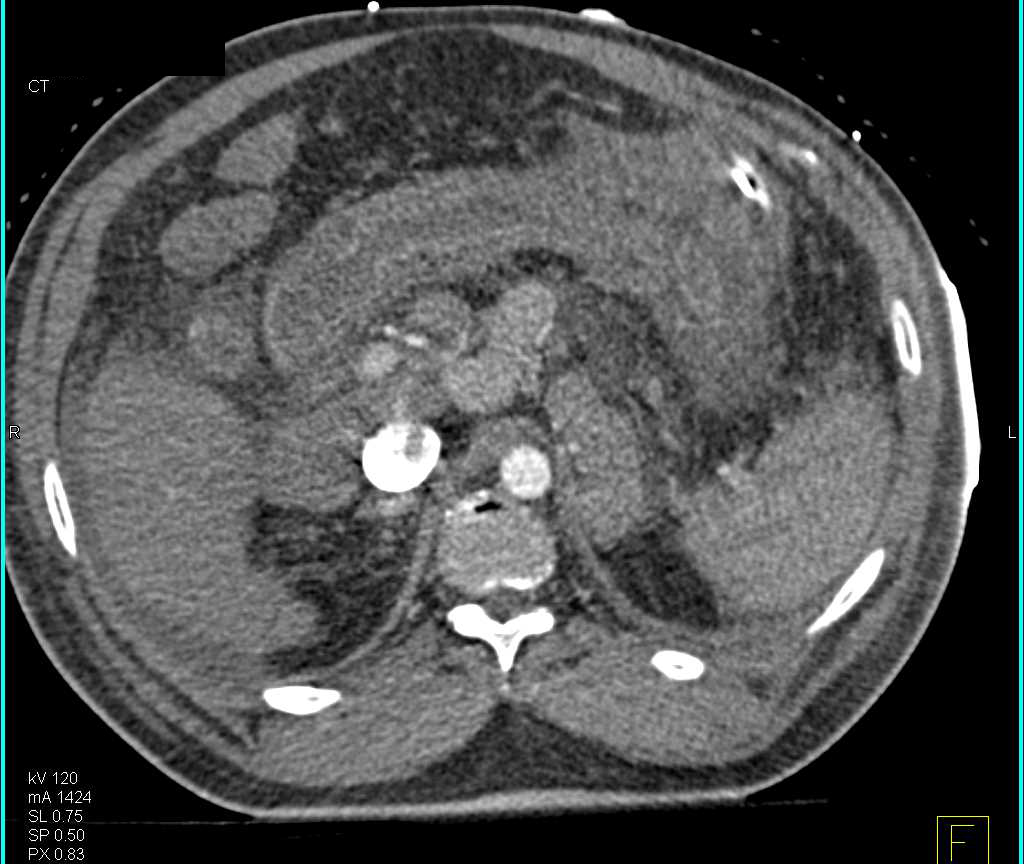

Perforated Duodenum Post Endoscopic Retrograde Cholangiopancreatography (ERCP)